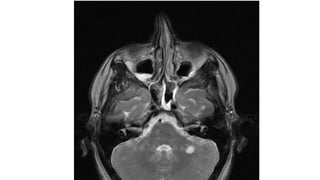

Spinal Lesions

cord lesion